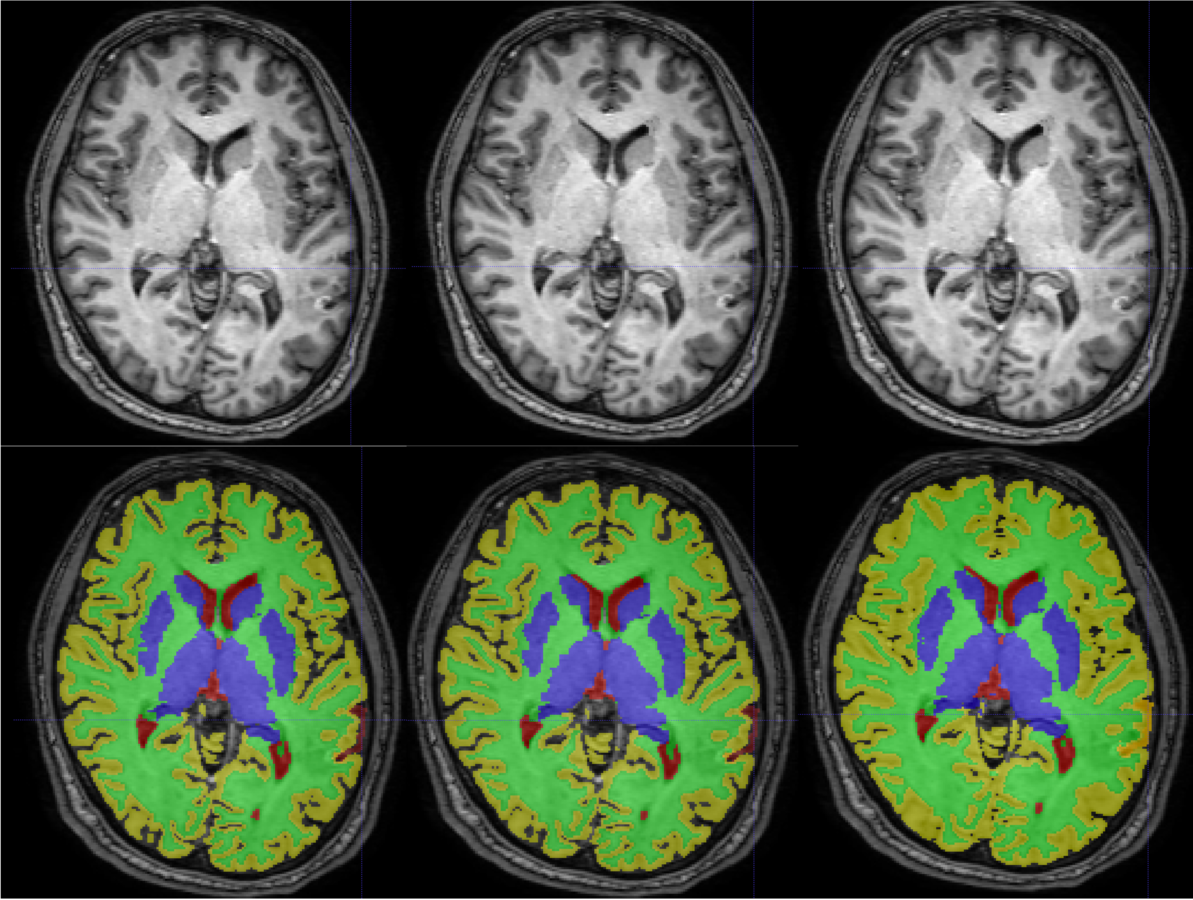

Segmentation

Lesion filling algorithms in MS try to inpaint T1 hypo-intense WM lesion (about 30% of FLAIR-appearing lesions) as Normal-Appearing White Matter (NAWM).

This procedure has shown to improve:

- Segmentation reliability

- Cortical Thickness estimation in longitudinal studies.